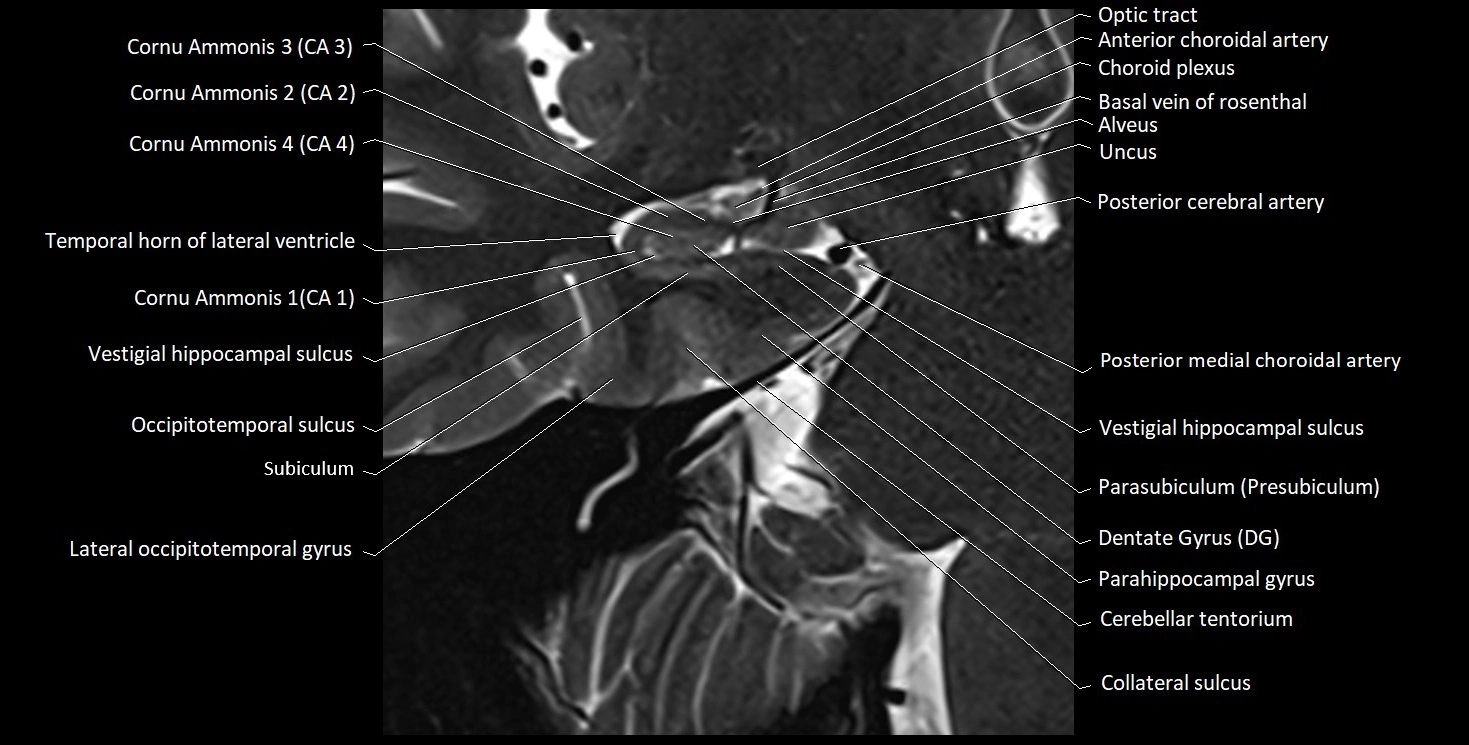

MRI images

image